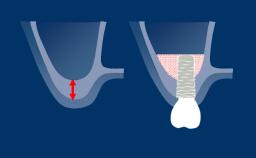

A radiologia é usada em Implantodontia para complementar e confirmar os achados clínicos. As radiografias podem ajudar no diagnóstico, planejamento do tratamento e na revisão de implantes dentários restaurados, em visitas regulares de manutenção. A imagem 3D mostrada aqui demonstra o nível de detalhe que pode ser obtido. No entanto, toda a radiação - incluindo raios-x - acarreta risco de danos aos tecidos e efeitos a longo prazo. Portanto, deve-se considerar os riscos associados à investigação onde a radiografia é planejada, que devem ser equilibrados com os benefícios esperados. Da mesma forma, deve-se considerar uma avaliação das necessidades de diagnóstico e planejamento do caso. A seleção da técnica radiográfica correta deve basear-se no equilíbrio entre as necessidades diagnósticas e o risco.